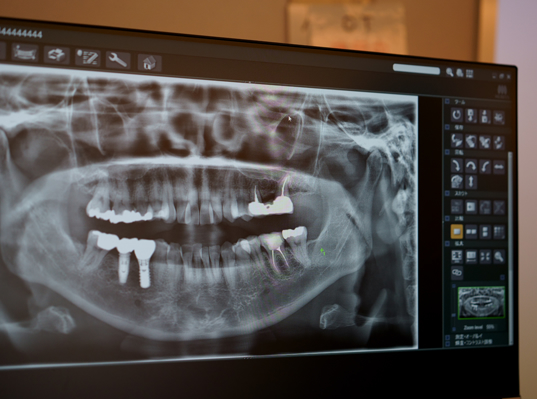

従来のX線写真が二次元的な平面画像であるのに対し、歯科用CTは三次元の立体画像であるため、より多くの情報が得られ、より精度の高い治療に役立てることができます。

従来のX線では見ることができない部位も多く、CTを使うことできっちり把握できます。

CTでは、歯の根の状態、上下顎の骨の形状と厚み、上顎洞までの距離、下歯槽間までの距離、顎関節の位置関係など細かく調べ把握することができます。患者様一人ひとりの状態を把握した上でインプラント治療を行なっております。そうすることで安心したインプラント治療を提供することができるのです。